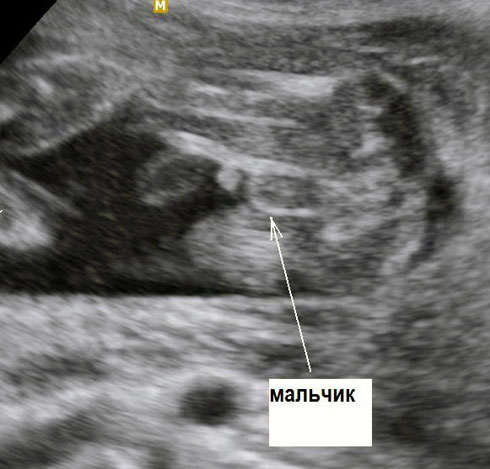

Особенности УЗИ при определении пола ребенка

Раздел: Идеи и советы